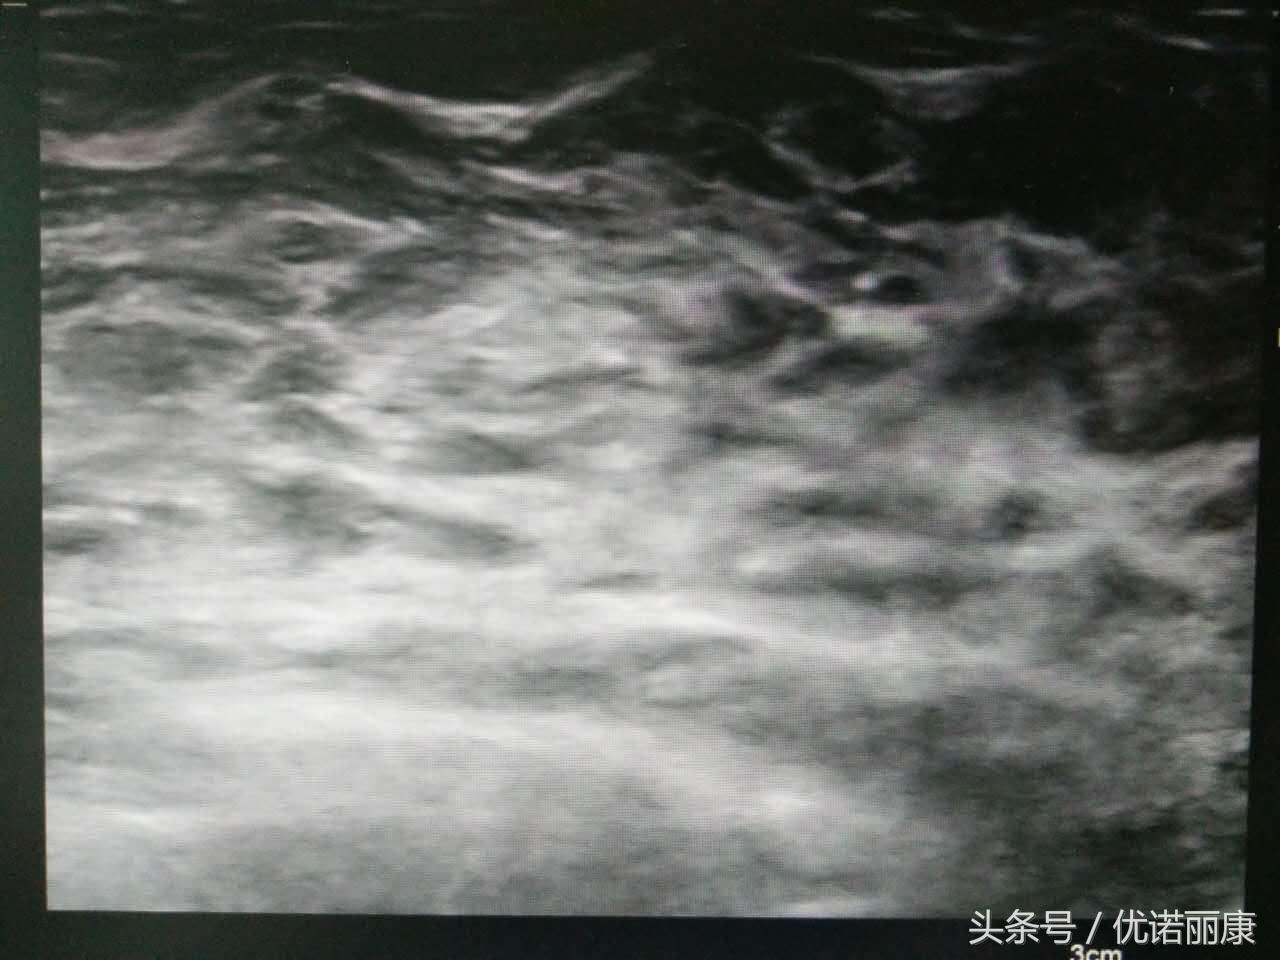

正常略增生图像

乳腺回声增粗,无肿块回声